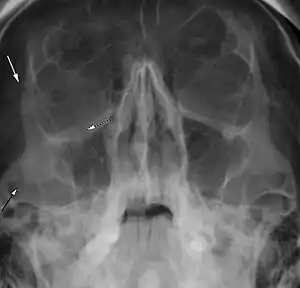

| Right zygomaticomaxillary complex fracture with disruption of the lateral orbital wall, orbital floor, zygomatic arch and maxillary sinus. | |